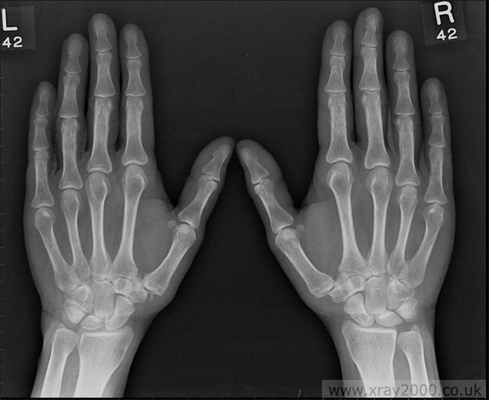

Остеоартроз мелких суставов кисти

Характеризуется следующими клиническими признаками:

- Наличие плотных узелков на боковых поверхностях дистальных межфаланговых суставов (узелки Гебердена) и на тыльно-боковой поверхности проксимальных межфаланговых суставов (узелки Бушара); Образование узелков сопровождается жжением, покалыванием, онемением (после завершения формирования узелков эти симптомы исчезают)

- Боль и некоторая скованность в суставах кисти, уменьшение объема движений.

- Прогностически наличие узелков Гебердена или Бушара является неблагоприятным признаком течения остеоартроза. (эта форма остеоартроза имеет генетическую детерминированность и передается по женской линии).

В принципе артроз может развиваться в любых суставах. В зависимости от того, поражение каких суставов преобладает, различают несколько форм артроза. При первой форме в основном поражаются мелкие суставы кистей и стоп. На пальцах образуются плотные узелки, так называемые узелки Гебердена. Эти узелки являются костными выростами по краям суставов. В стадии образования они могут быть болезненными, кожа над ними может краснеть. Затем воспаление стихает, сохраняются безболезненные деформации суставов, функция кисти сохраняетсяудовлетворительной.

Как правило, первыми болезни “сдаются” суставы пальцев, расположенные за ногтями (последняя фаланга пальцев), а также суставы больших пальцев рук. На них появляются безболезненные, но заметные утолщения - т.н. узлы Бушара и узлы Гебердена, - которые легко заметить на тыльной стороне кисти. Часто кожа на них краснеет, становится горячей.